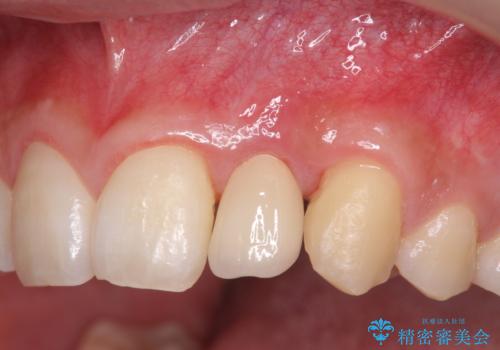

- [ 再生治療・歯周外科・小矯正・セラミック補綴 ] 前歯の歯周病治療- 担当医 大元洋佑 ![[ 再生治療・歯周外科・小矯正・セラミック補綴 ]  前歯の歯周病治療の症例 治療前](https://seimitsushinbi.jp/wp/wp-content/uploads/2022/12/83065c2454a29ed71cf190e15a6106f4-500x350.jpg?v=1671673398) ![[ 再生治療・歯周外科・小矯正・セラミック補綴 ]  前歯の歯周病治療の症例 治療後](https://seimitsushinbi.jp/wp/wp-content/uploads/2022/12/ec16e37ee53325a6f6629b94759f5513-500x350.jpg?v=1671673454)